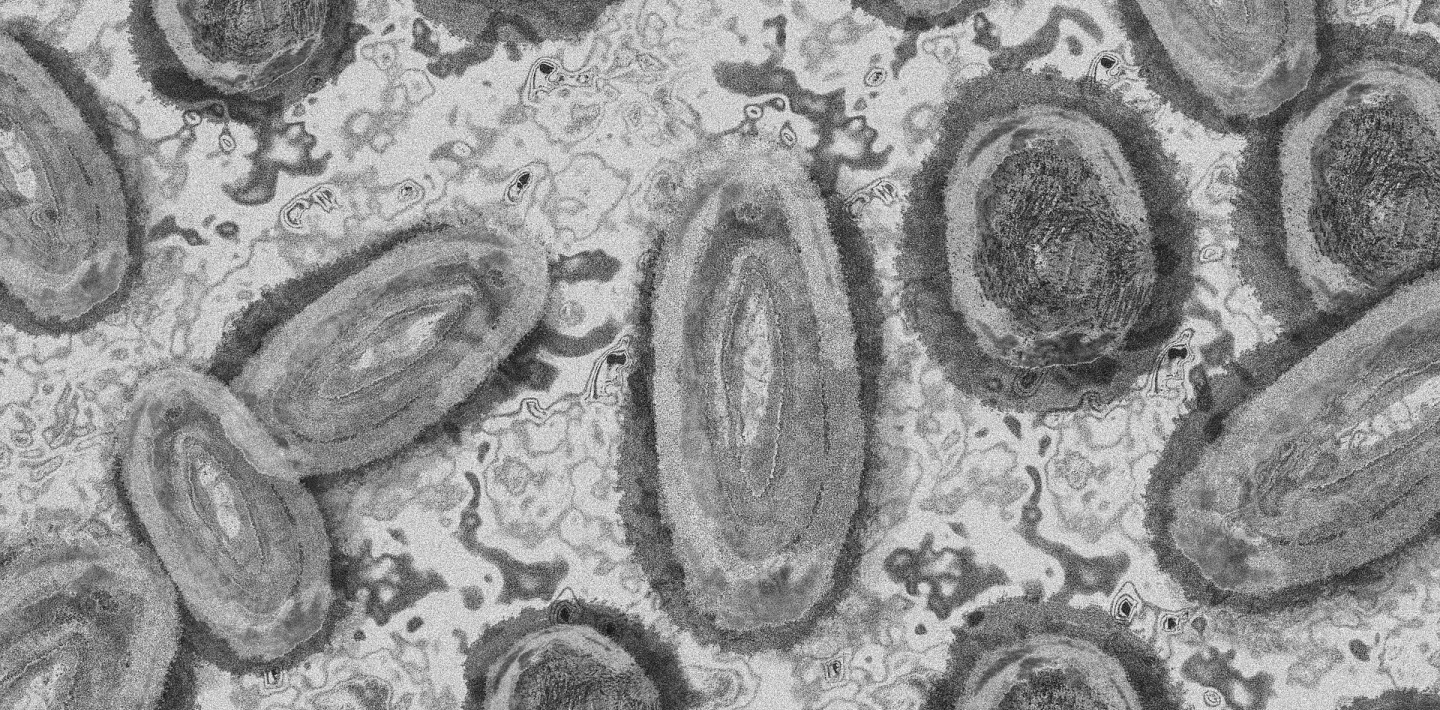

Aufnahme von Affenpocken

Affenpocken sind eine virale Infektionskrankheit. Mehr dazu.